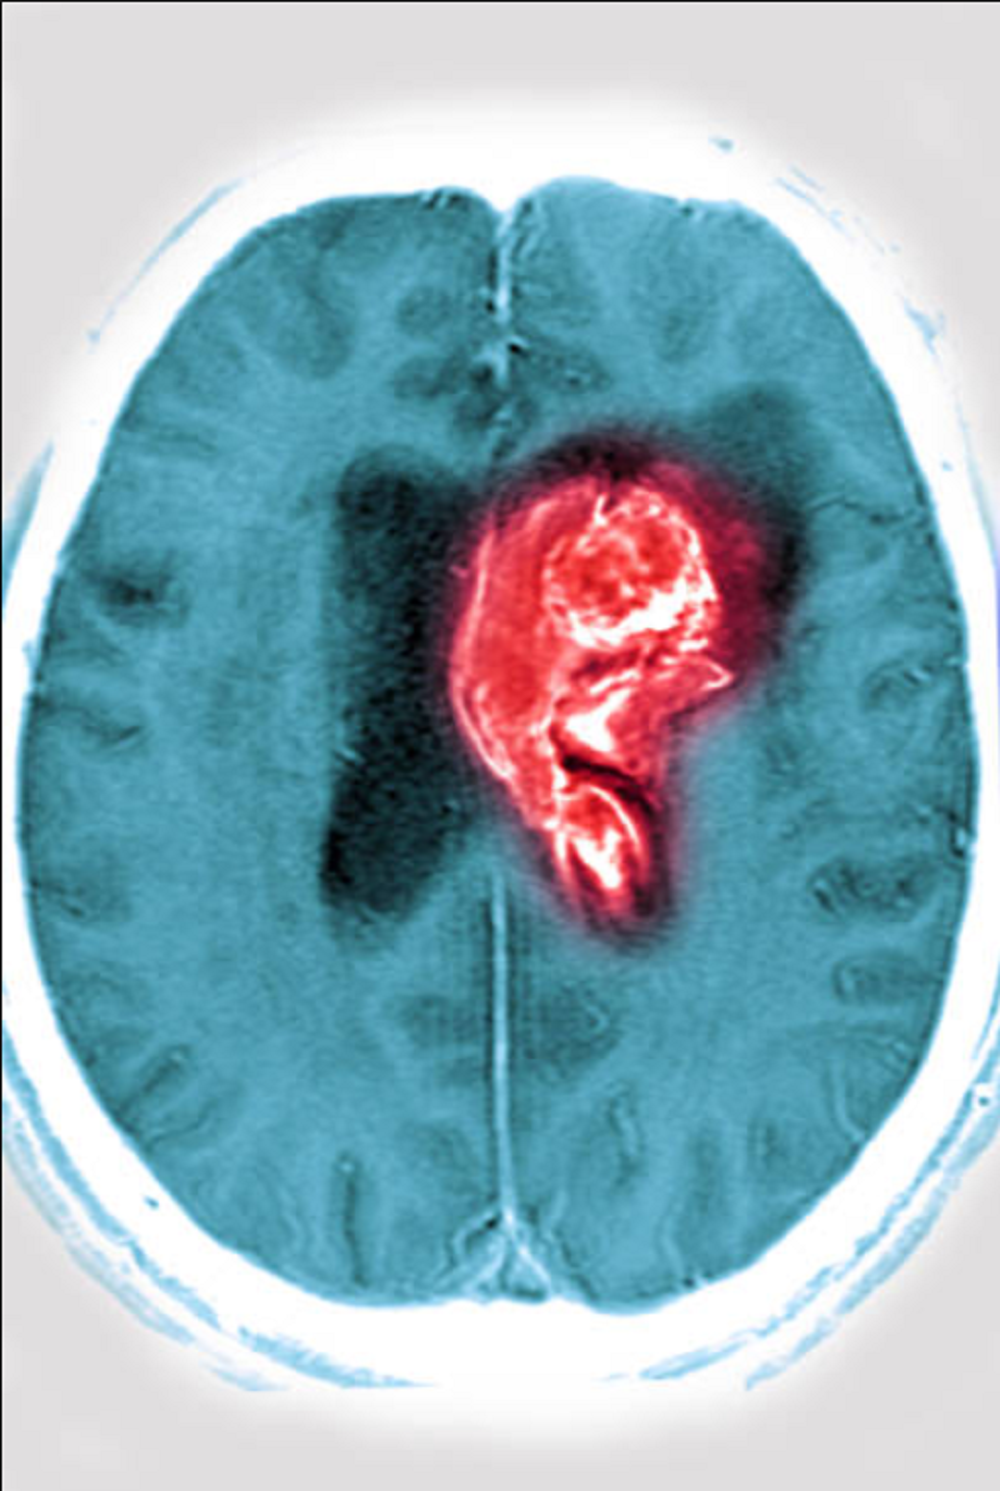

El neurólogo explicó que existen dos tipos principales de accidente cerebrovascular. El ACV hemorrágico —o hemorragia cerebral— es el resultado de la ruptura de una arteria cerebral, lo que provoca una acumulación de sangre. El ACV isquémico, por su parte, se produce por la obstrucción de una arteria, lo que impide la llegada de sangre a una zona del cerebro, matando así las neuronas por falta de oxígeno y nutrientes.

El diagnóstico temprano, generalmente a través de estudios de imagen como la tomografía o la resonancia magnética, es esencial para determinar el tratamiento adecuado. En casos extremos, se precisa neurocirugía para drenar hematomas y reducir la presión intracraneal. Sin embargo, el Dr. Linazasoro considera que la prevención es la herramienta más efectiva para reducir la incidencia de estos eventos y evitar la manifestación de los cinco síntomas de ACV.